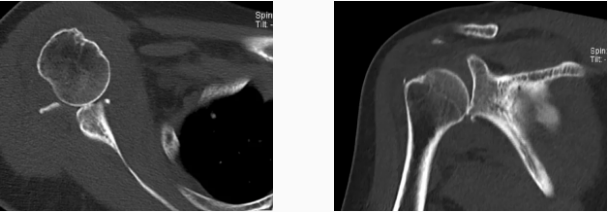

病例2

病史摘要:女性,65歲,跌傷致右肩活動受限9天。

MR圖示:右側(cè)肱骨頭后上部局部明顯凹陷,骨皮質(zhì)欠光整,周圍見片狀壓脂高信號影(箭頭);前盂唇脫離移位;前下盂唇不連,局部骨質(zhì)分離(三角形);肱骨頭向前移位。